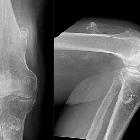

Kartilaginäre

Exostosen an Femur, Tibia und Fibula. Synostose zwischen Tibia und Fibula. Röntgenbild ap.

Exostosen an Femur, Tibia und Fibula. Synostose zwischen Tibia und Fibula. Röntgenbild seitlich

Typische

kartilaginäre Exostose mediale proximale Tibia mit breiter Basis und kontinuierlicher Fortsetzung der Spongiosa in die Exostose.